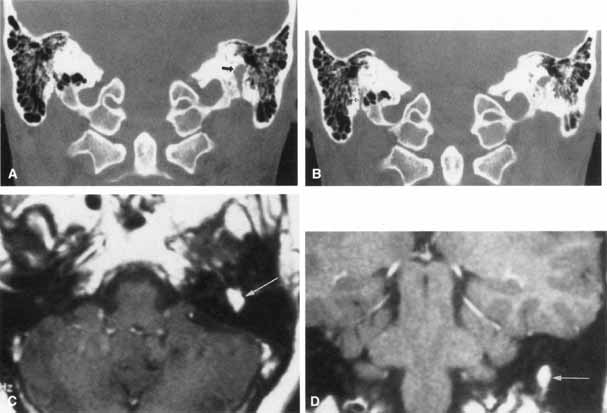

FACIAL NEUROMA The facial paralysis associated with facial nerve neuromas usually has a gradual onset, but it may be more rapid, simulating idiopathic facial paralysis. Indeed, the pareses may fluctuate or may be associated with hemifacial spasm. In some cases, hearing loss precedes the onset of facial weakness, thereby simulating an acoustic neuroma.93 CT scan typically shows a uniformly enhancing mass in the fallopian canal. T2-weighted MRI images may show a hyperintense mass in the facial canal89 that enhances with gadolinium on T1-weighted images (Fig. 16). The ultimate diagnosis of facial neuroma requires surgical exploration and biopsy. Biopsy usually results in facial paralysis. This possibility should be discussed with the patient before surgery. Facial function recovery after resection of tumor and grafting, although never normal, may include restored tone, symmetry, and weak voluntary movement. The more facial function present before surgery, the better the results with grafting. This observation must be shared with the patient, because he or she might elect to wait until facial function is lost before consenting to surgical removal. When the tumor is located eccentrically, removal is possible with preservation of facial function.94 METASTATIC LESIONS A history of cancer (particularly involving the breast, lung, thyroid, kidney, ovary, or prostate) associated with a rapidly progressive facial paralysis strongly suggests a metastatic lesion. The facial nerve may be involved by a bony metastasis or by meningeal infiltration. Neuroimaging studies are indicated to search for the primary site and to localize the site of facial nerve involvement (Fig. 17). If these are unrevealing, serial lumbar punctures may be necessary to exclude meningeal carcinomatosis. In some cases, surgical exploration of the temporal bone or of the extracranial course of the facial nerve is recommended to locate the lesion. In one study of meningeal carcinomatosis, the seventh nerve was affected in 15 of 90 patients.95 Facial nerve involvement is often unilateral, but it occurs bilaterally in about 10% of such patients.96

| A wide variety of spontaneous, anomalous facial movements occur with surprising

Although the underlying pathophysiology of this disorder is unknown, the concept of ephaptic transmission remains a dominant theory.132–134 Ephaptic transmission refers to a lateral spreading of neural impulses by damaged axons that excite adjacent nerve fibers. This leads to the spontaneous and simultaneous contraction of adjacent facial muscles. Anomalous facial motor nucleus firing is an alternative theory. Ferguson135 has suggested that damage to the facial nerve near its root entry zone, or in the brain stem, leads to deafferentation of the facial motor nucleus. This would result in augmented and automatic firing of the facial motor nucleus, presumably by disinhibition and reorganization of the central nuclear pool. Other cases are recorded after idiopathic palsy and with extramedullary compression by tumor.136 Neuroradiologic imaging, especially MRI of the posterior fossa, should be performed to exclude compression of the facial nerve by tumor (Fig. 24). magnetic resonance tomographic angiography is currently the most sensitive test to detect vascular compression of the seventh nerve at its exit zone.131,137 Neurosurgical treatment is directed toward decompression of the facial trunk at its exit from the brain stem in proximity to a tortuous or dolichoectatic anteroinferior cerebellar, posteroinferior cerebellar, vertebral, or basilar artery (see Fig. 24).10 The surgical approach is by way of a suboccipital craniotomy with placement of a sponge prosthesis between the facial nerve and the offending artery. In a series of 54 patients, Auger and colleagues138 reported complete relief in 70% of patients who underwent microvascular decompression for hemifacial spasm; 11% had initial improvement followed by a recurrence of facial spasm within 2 years, whereas another 9% had improvement without total resolution. Only 9% of patients showed no benefit. The mean follow-up period was 3.9 years. Complications included unilateral hearing loss, transient and permanent facial weakness, facial numbness, and unsteady gait. In a series of 310 patients treated by microvascular decompression of the facial nerve, over 90% had complete relief of spasm with a late recurrence of only 1%.139 Other surgical approaches include unilateral myectomy 140 and facial neurotomy.124 Medical therapy with carbamazepine141 and baclofen142 has also been successful in relieving hemifacial spasm in some patients. Injection of botulinum A toxin into the orbicularis oculi muscle has become standard treatment of hemifacial spasm.128 FACIAL SYNKINESIS When a patient suffers a seventh nerve paresis, he or she may subsequently demonstrate ipsilateral involuntary narrowing of the palpebral fissure upon volitional contraction of the orbicularis oris (Fig. 25) and other facial muscles (i.e., during pursing the lips, forceful opening of the mouth, smiling, or chewing with the mouth closed). In addition, lower facial muscles may contract during volitional eye closure. This phenomenon is due to aberrant regeneration of the seventh nerve with sprouting of axons to supply more than one muscle group. Frueh143 used electromyography to show that the narrowing of the palpebral fissure was secondary to contraction of the ipsilateral orbicularis oculi muscles and not due to inhibition of the levator superioris. At present, there is no effective way to prevent intrafacial synkinetic phenomena. Injections of botulinum toxin into the orbicularis oculi muscle may provide temporary relief.128